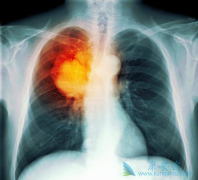

晚期肺癌患者吃EGFR-TKI吉非替尼出现肝毒性的原因是什么?

在目前已经公布的不同EGFR-TKI治疗晚期肺癌的III期临床研究中,药物性肝损伤(DILI)的发生率为5%-55.3%,≥3级的发生率为0.4%-26.3%。除阿法替尼外,多数 EGFR-TKI 主要通过肝脏酶系代谢。有研究认为EGFR-TKI的肝毒性与其活性代谢产物的代谢有关,而诱 ...